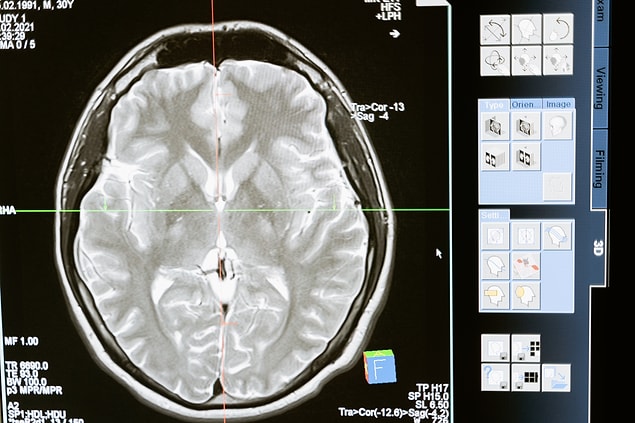

Zekâyla Bağı Olduğu Argüman Ediliyor: Yeni Bilgiler Öğrenmek Hakikaten de Beyin Kıvrımlarını Artırıyor mu?

Beyin kıvrımlarının nasıl oluştuğuyla ilgili bilimsel bir kanıt yok. Lakin bu kıvrımlar, insan şimdi anne karnındayken gelişmeye başlıyor. Anne rahminde bulunan bir bebeğin beyin yapısı, birinci başlarda düz iken vakitle kıvrımlar kazanarak gelişiyor. Doğum vakti yaklaşırken kıvrımlar artık tüm çizgileriyle bariz hâle geliyor. Gelişimini tamamlamış herkesin beyni kıvrımlı yapısını koruyor fakat beyinde rastgele bir sıhhat sorunu meydana gelirse kıvrımlı yapıda da değişiklikler gözlemlenebiliyor. Ender beyin hastalıklarına sahip kimi bireylerde ise beyin kıvrımları olmayabiliyor ya da gerekli ölçüde gelişemeyebiliyor.

Beyin kıvrımları hal değiştirir mi?

Kafaya alınan darbeler, kurşunlu yaralanmalar, ameliyatlar ve gibisi fizikî tesirler olmadığı sürece beyinde bulunan kıvrımlar değişmiyor. Lakin beyin geliştikçe nöronlar ortası ilişkiler artabiliyor ve beyin esneklik kazanabiliyor. Bu durum yalnızca beşerler için değil, hayvanlar için de geçerliliğini koruyor.

Doğduğumuz an beynimizde ne kadar kıvrım varsa o kıvrımlar hayatımız boyunca bizimle kalıyor. Münasebetiyle kıvrım sayısında, hiç durmadan yeni bilgiler öğrensek de, rastgele bir artış ya da azalış meydana gelmiyor. Yani, yeni bilgiler edinmekle beyin kıvrımları ortasında sanıldığı üzere bir ilgi yok. Ayrıyeten kıvrım sayısı konusunda net bir söz kullanılamıyor zira bu sayı her bireyde farklı olabiliyor. Bunun nedeninin ise kafatasının hacmi ve yapısı olduğu kestirim ediliyor.